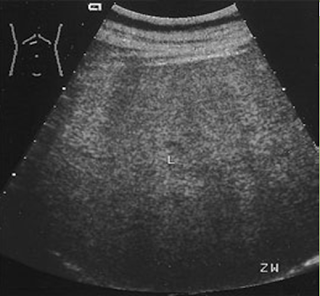

Fatty liver is an acquired but reversible disorder of metabolism. Fatty filtration implies increased lipid accumulation in the hepatocytes.

What is the sonographic appearance of fatty filtration?

Increased echogenicity

Enlargement

of the lobe.

Decreased penetration

Difficult to

image

Increased echo texture